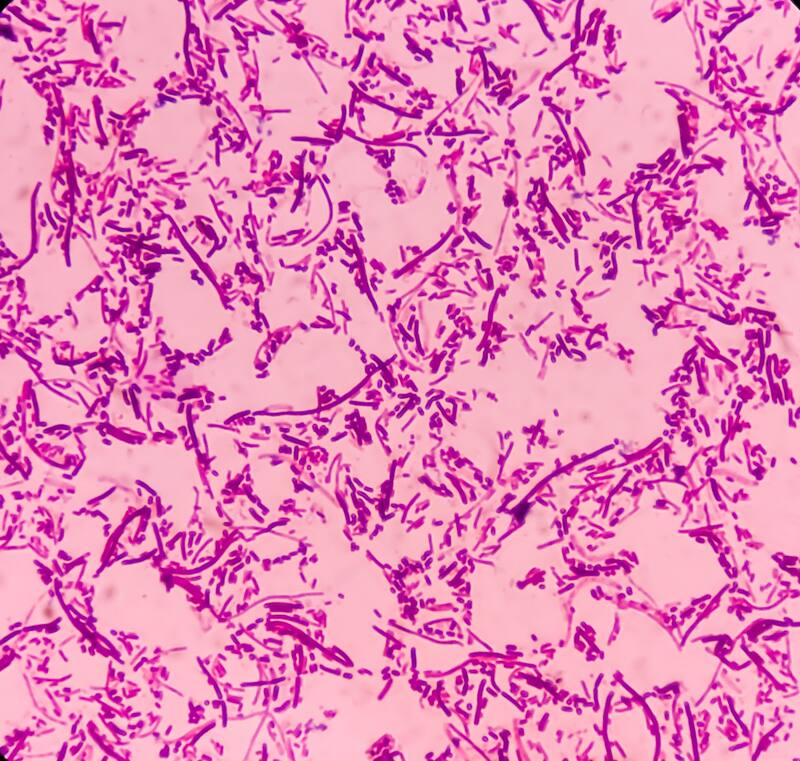

La salmonelosis es una infección bacteriana que puede causar enfermedades gastrointestinales, cuyos síntomas suelen aparecer entre 12 y 72 horas después de la infección y pueden incluir fiebre, diarrea, vómitos y dolor abdominal.